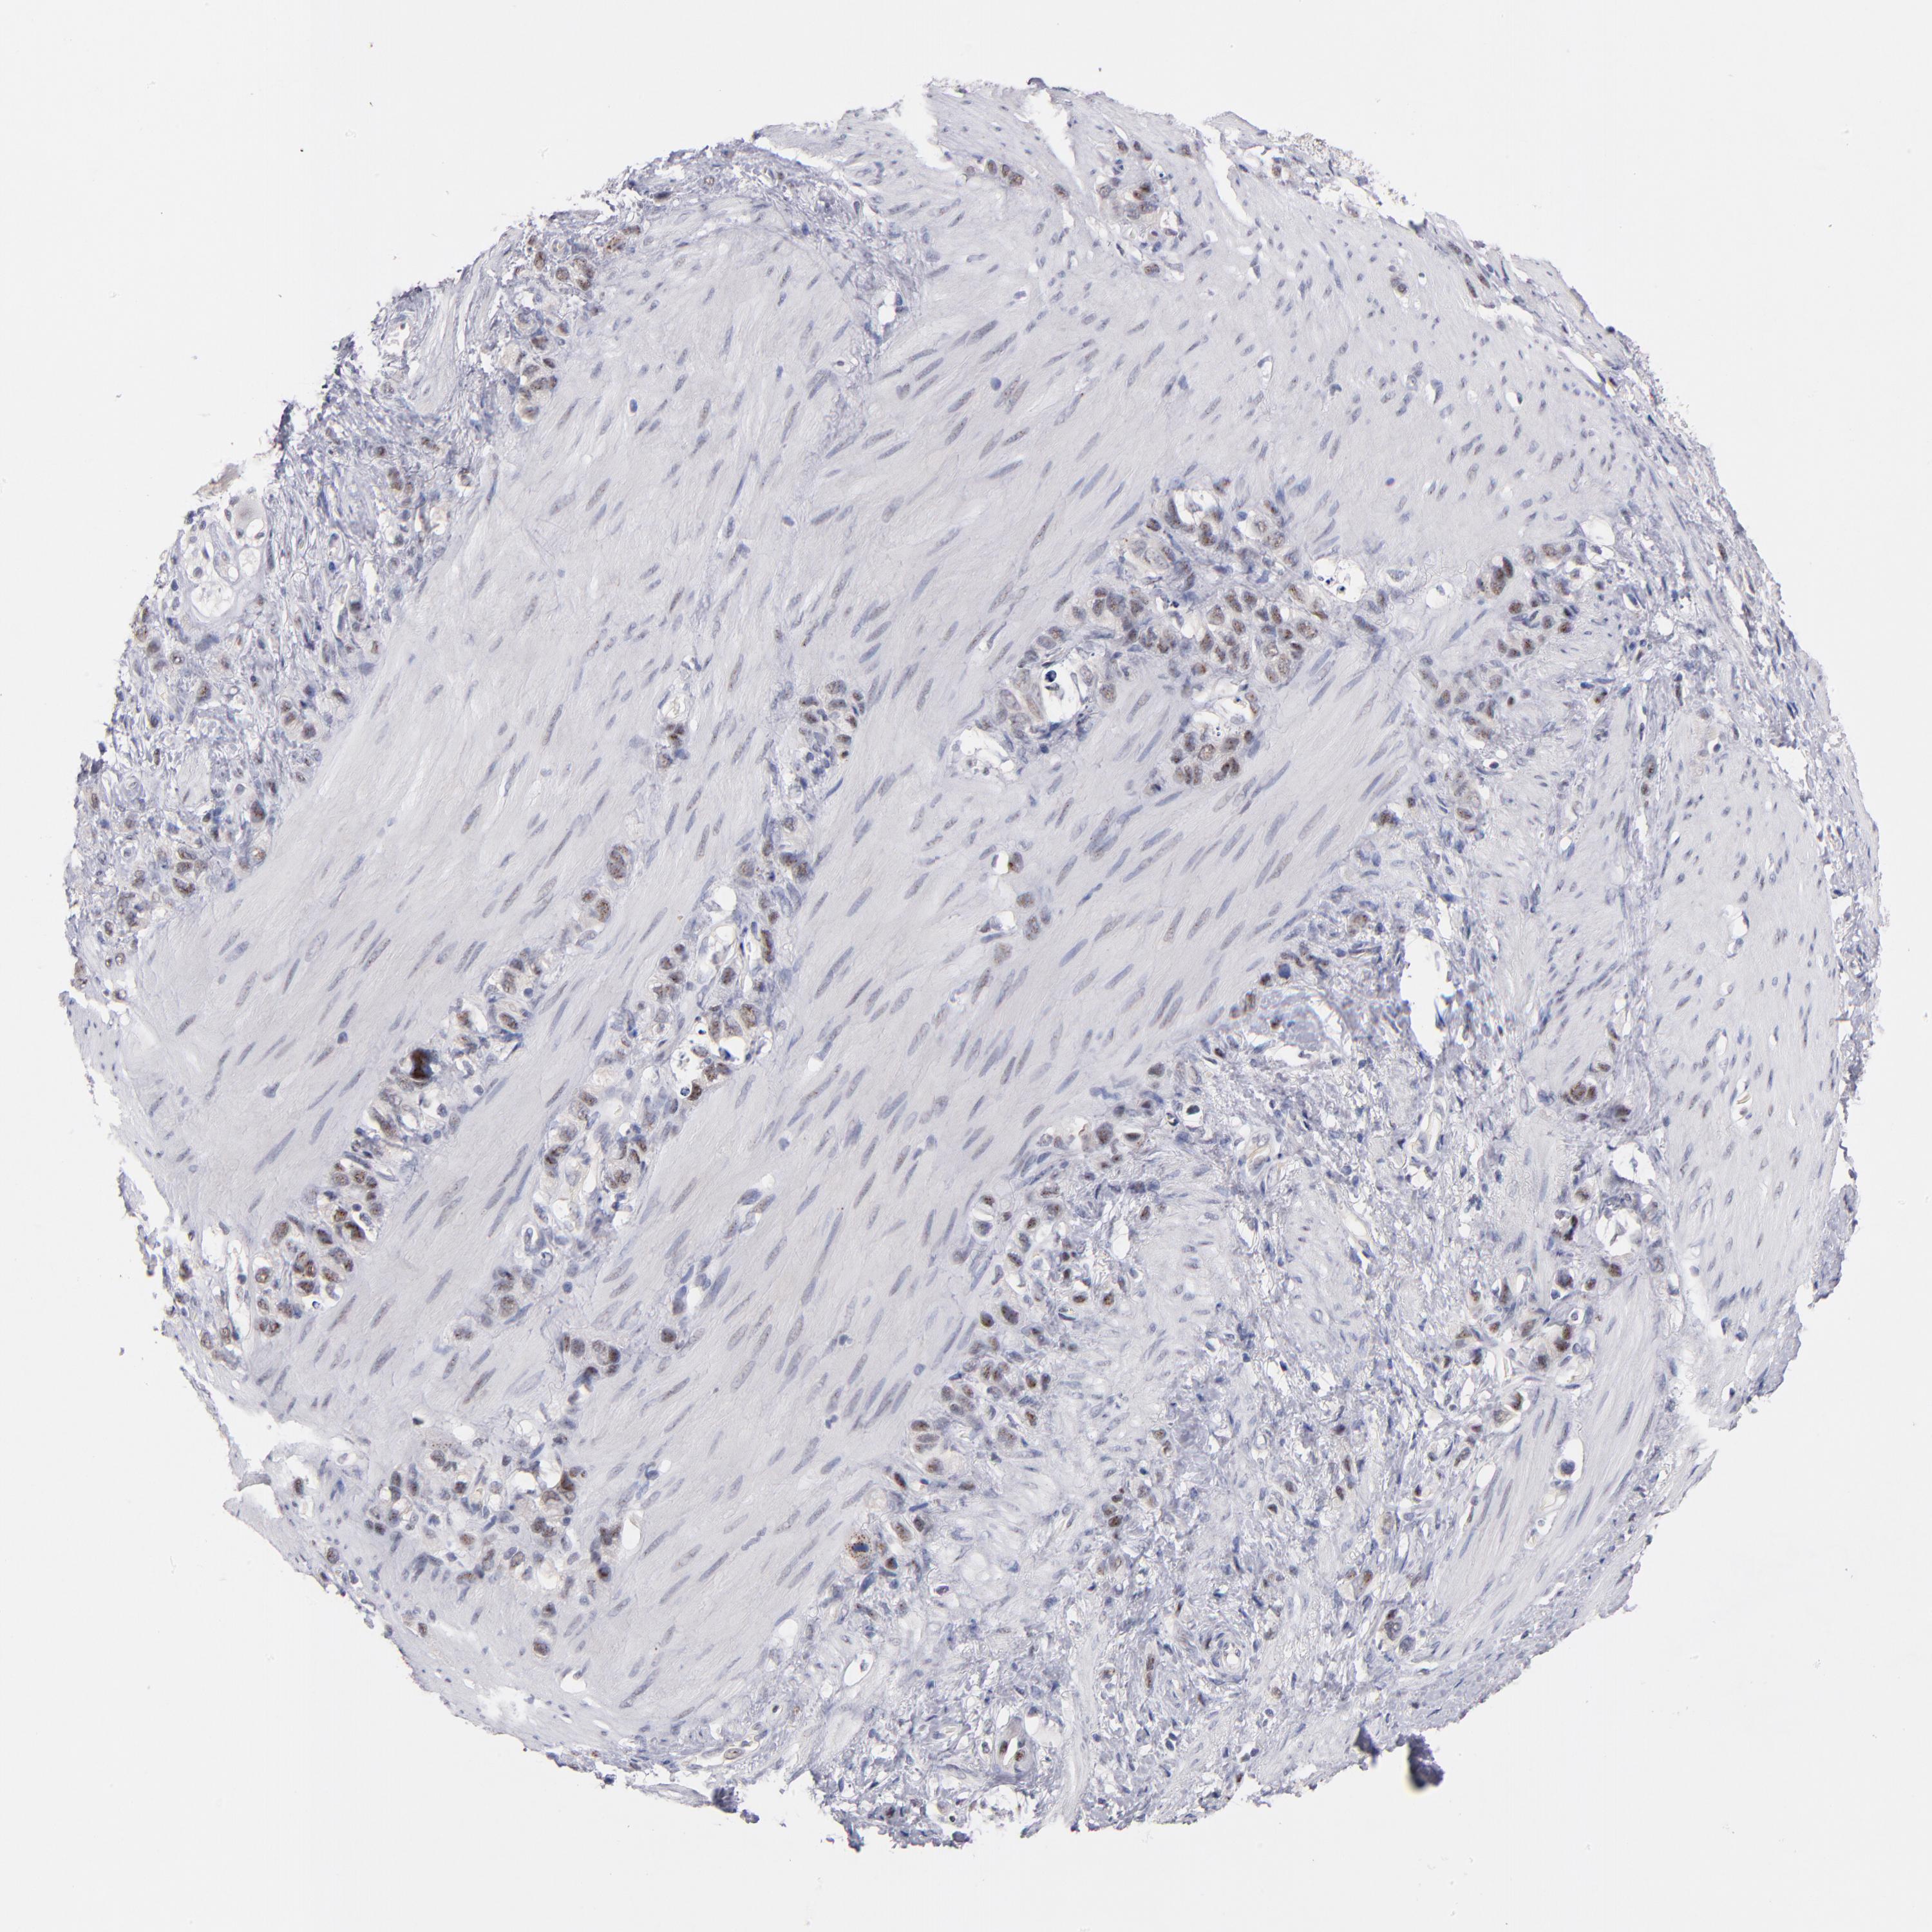

STOMACH CANCER - Protein expressioni

A mouse-over function shows sample information and annotation data. Click on an image to view it in a full screen mode. Samples can be filtered based on level of antibody staining by selecting one or several of the following categories: high, medium, low and not detected. The assay and annotation is described here.

Note that samples used for immunohistochemistry by the Human Protein Atlas do not correspond to samples in the TCGA dataset.

Antibody stainingi

Antibody staining in the annotated cell types in the current human tissue is reported as not detected, low, medium, or high, based on conventional immunohistochemistry profiling in selected tissues. This score is based on the combination of the staining intensity and fraction of stained cells.

Each image is clickable and will lead to virtual microscopy that enables deeper exploration of all samples and also displays staining intensity scores, fraction scores and subcellular localization as well as patient and tissue information for each sample.

Antibody HPA002640

Antibody CAB019291

Antibody CAB080384

Staining

High

Medium

Low

Not detected

Intensity

Strong

Moderate

Weak

Negative

Quantity

>75%

75%-25%

<25%

None

Location

Nuclear

Cytoplasmic/membranous

Cytoplasmic/membranous,nuclear

Adenocarcinoma, NOS

Adenocarcinoma, High grade